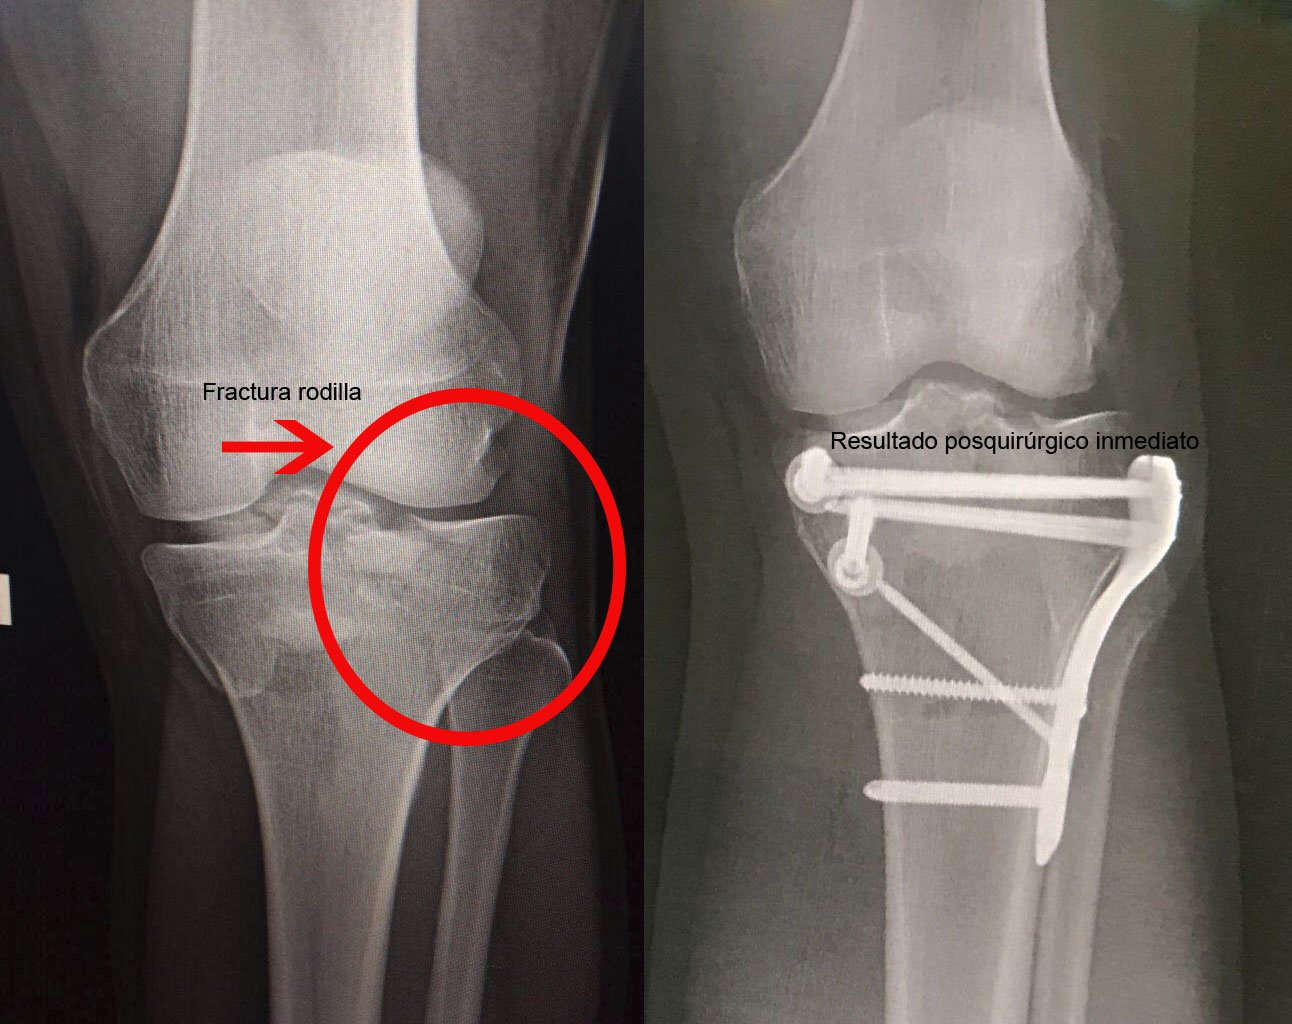

Una fractura ósea es la ruptura de un hueso, la cual puede presentarse por diversas causas y su tratamiento dependerá de la magnitud, sitio anatómico y de las enfermedades concomitantes. Algunas pueden manejarse de forma conservadora con solo inmovilización y hay otras que requieren de un tratamiento quirúrgico. A continuación, podrá ver algunos casos quirúrgicos, dando clic a la zona del cuerpo afectada.